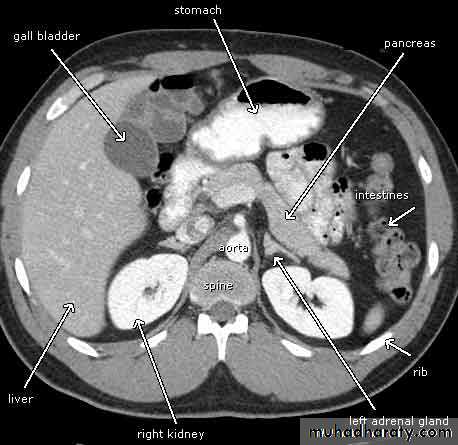

CT abdomen